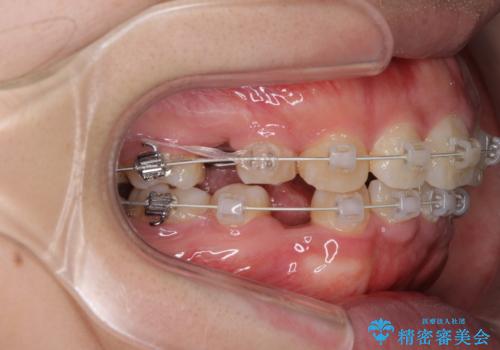

がたがたと出っ歯を直したい ワイヤーによる抜歯矯正

- ガタガタと出っ歯を主訴に来院されました。

上下左右の歯を1本ずつ、合計4本抜歯してワイヤーにて矯正治療をすることとなりました。

前から4番目の歯を抜歯することが多いのですが、右上の前から5番目の歯が神経の治療済みであり、こちらの歯を抜歯する計画としました。

通常より治療期間を要しましたが、健康な歯を残すことができました。